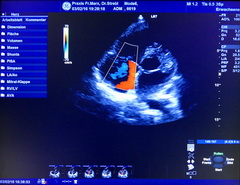

Herzecho / Ultraschalluntersuchung

Die Echokardiographie ist eine Ultraschalluntersuchung des Herzens. Sie ist ein wichtiges Untersuchungsverfahren bei der Abklärung von Herzschwäche, Herzklappenerkrankungen, Herzmuskelentzündungen, Herzrhythmusstörungen, unklarer Atemnot und Bluthochdruck.